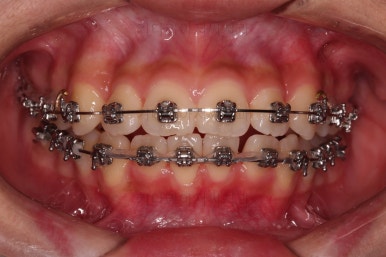

이번 환자분이 선택한 장치는 엠파워 메탈이라고 하는 자가결찰 금속 브라켓입니다.

메탈 브라켓이라고 다 구식의 안좋은 장치가 아닙니다.

"자가결찰" 브라켓이면 모두 우수한 성능의 장치인데요.

철사를 잡아주는(결찰) 캡이 브라켓에 달려 있어 스스로 묶을 수 있는(자가) 브라켓입니다.

즉, 세라믹 중에서도 자가결찰인 것이 있고 아닌 것이 있으며, 메탈 중에서도 자가결찰인 것이 있고 아닌 것이 있습니다.

윗니가 가지런해진 뒤에는 부산치아교정치과 키다리아저씨치과에서는 ABP라고 하는 장치를 사용해 주면서 아랫니에도 브라켓을 부착합니다.

깊게 물리는 과개교합을 개선하기 위함인데요.

과개교합을 개선하기 위해서는 미니스크류를 사용하기도 하고 ABP를 사용하기도 하며, 윗니 앞니를 코 방향으로 밀어넣기도 합니다.

얼굴모습과 교합을 생각해서 각 케이스마다 모두 다른 방법을 적용해야 하므로 일관된 공식이 있는 것이 아닙니다.

이번 환자분은 ABP의 사용이 가장 적합했던 케이스였습니다.

ABP를 사용하지 않고도 과개교합이 매우 좋아졌고요.

위아래 치열이 매우 고르게 되었으며, 이제부터는 발치공간을 줄여나가면서 교합을 맞춰 나가면 됩니다.